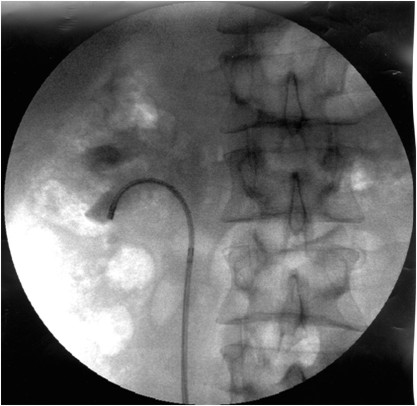

Интраоперационная рентгенография: фиброуретеропиелоскоп в полостной системе почки

Антеградная биопсия слизистой лоханки почки